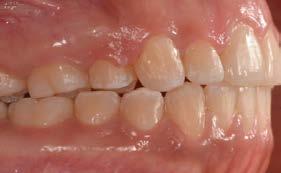

Figura 1. Fotografías intraorales: a) arcada superior, b) oclusión lateral derecho y c) oclusión central, d) oclusión lateral izquierdo y e) arcada inferior.

Figura 2. Planeación en tomografía axial computarizada: a) vista sagital, b) vista transversal, c) vista 360°, d) reconstrucción 3D y e) ortopantomografía.

Al examen intraoral se observa arcada dental incompleta; con ausencia de órganos dentales 16 y 27 (Figura 1).